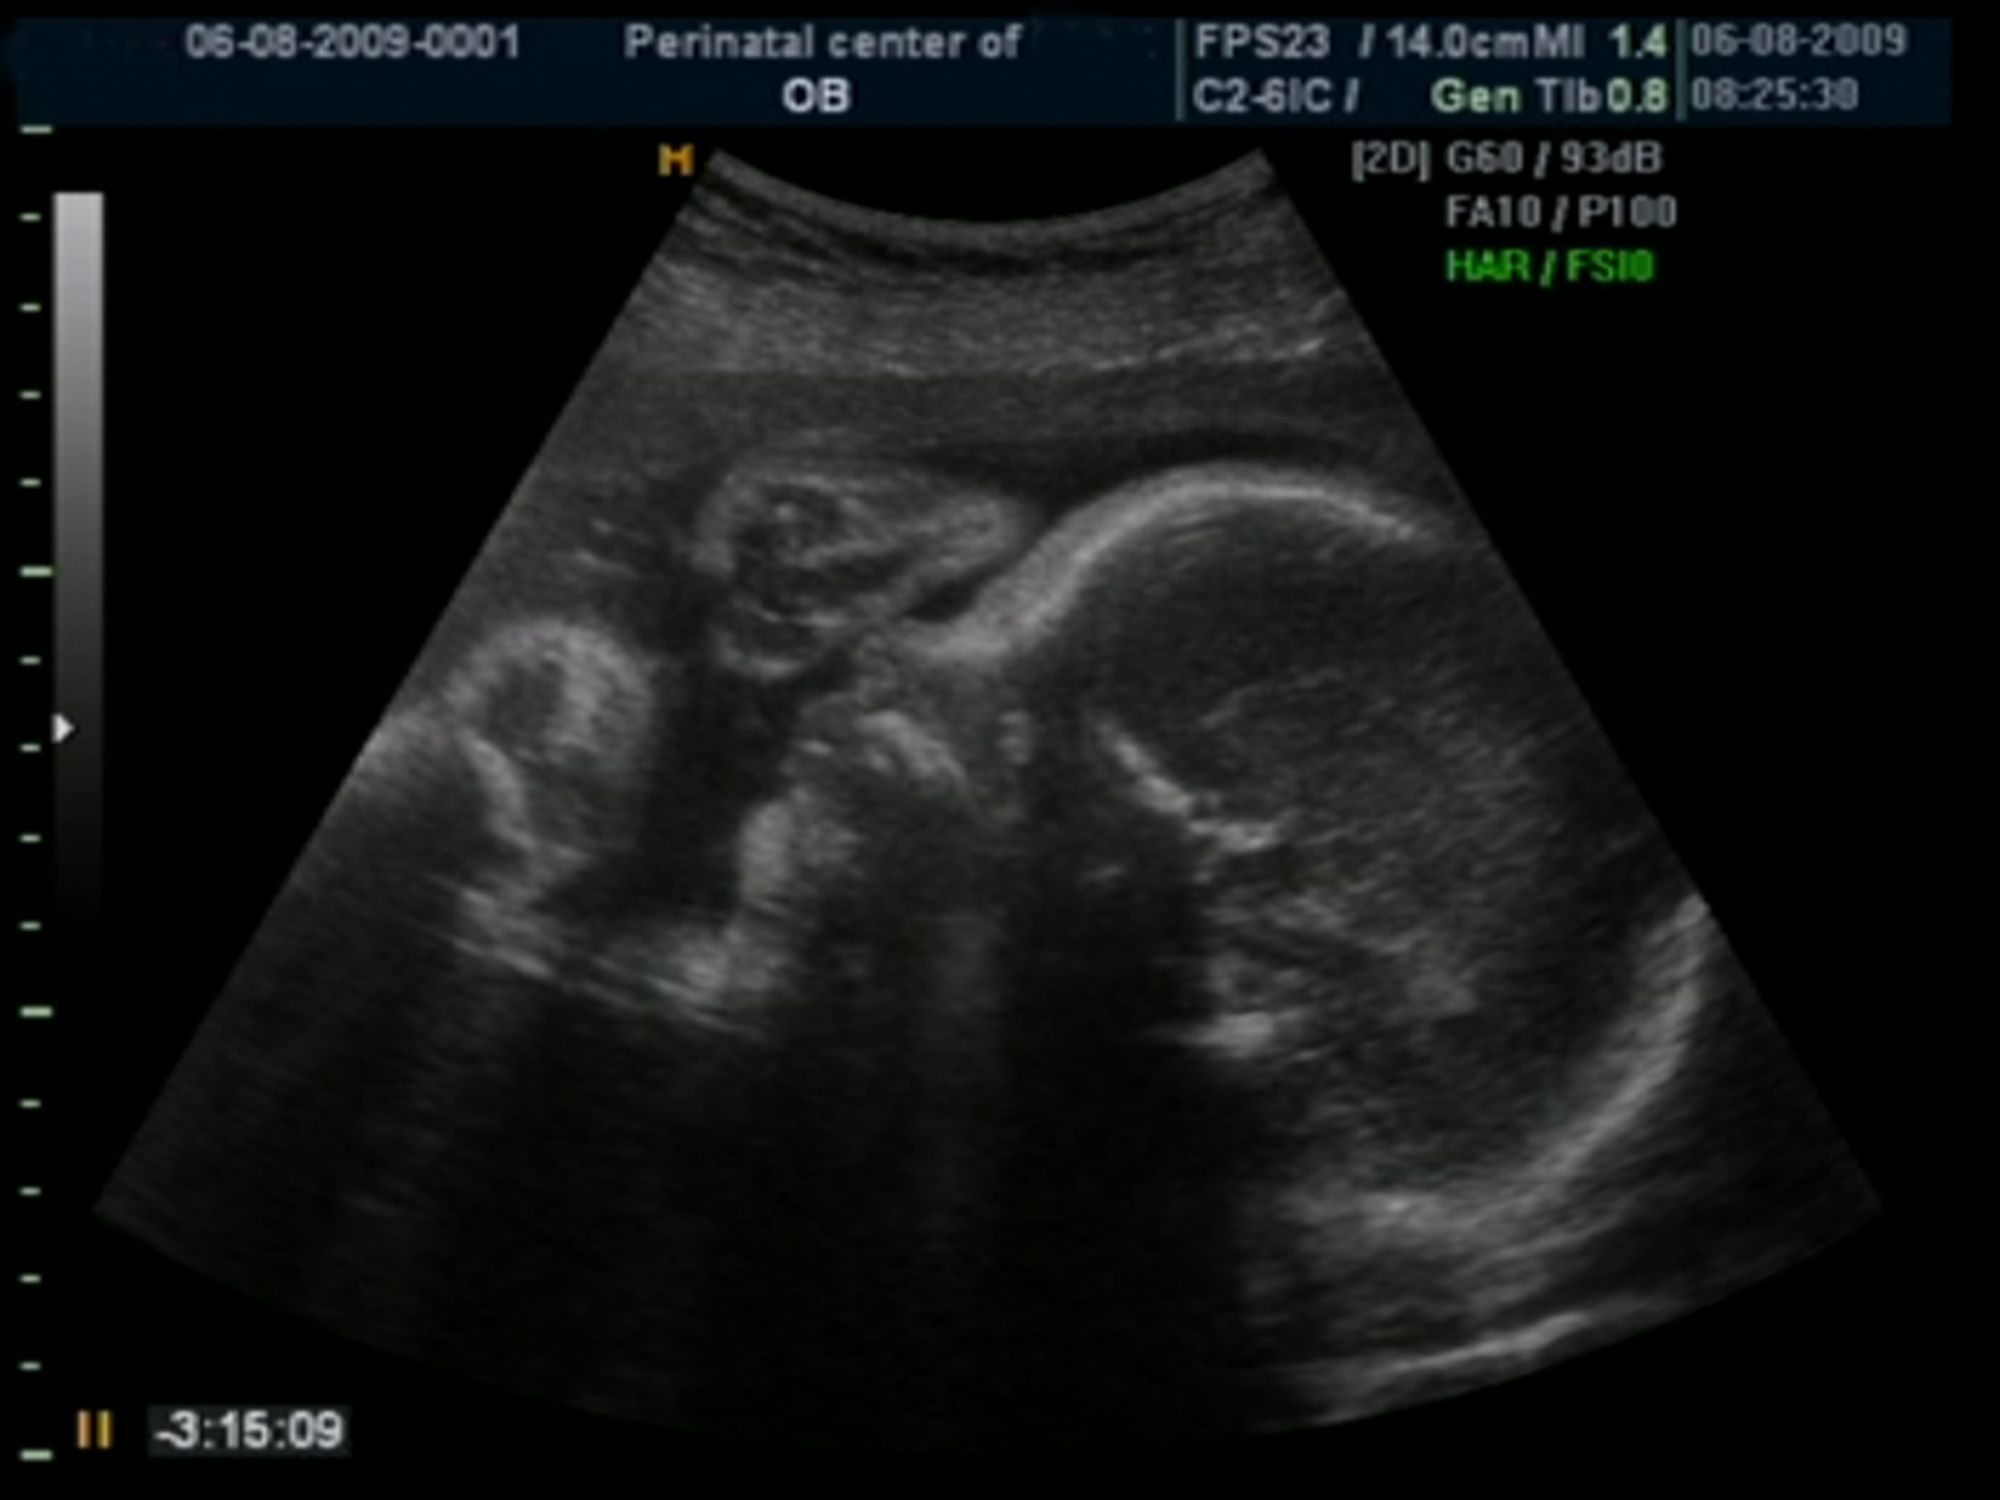

По определению врачей, неразвивающаяся (она же замершая) беременность это патология, при которой развитие эмбриона (в первые недели) или плода полностью прекращается в силу его гибели. У такого плода нет сердцебиения, все процессы обмена веществ остановлены, нет процессов деления клеток и роста.

Иногда неразвивающаяся беременность называется, не совсем верно с точки зрения физиологии, несостоявшимся выкидышем. При этом есть смерть плода, а признаков выкидыша с тонусом матки, кровотечением и отслойкой плодного яйца не наблюдается.